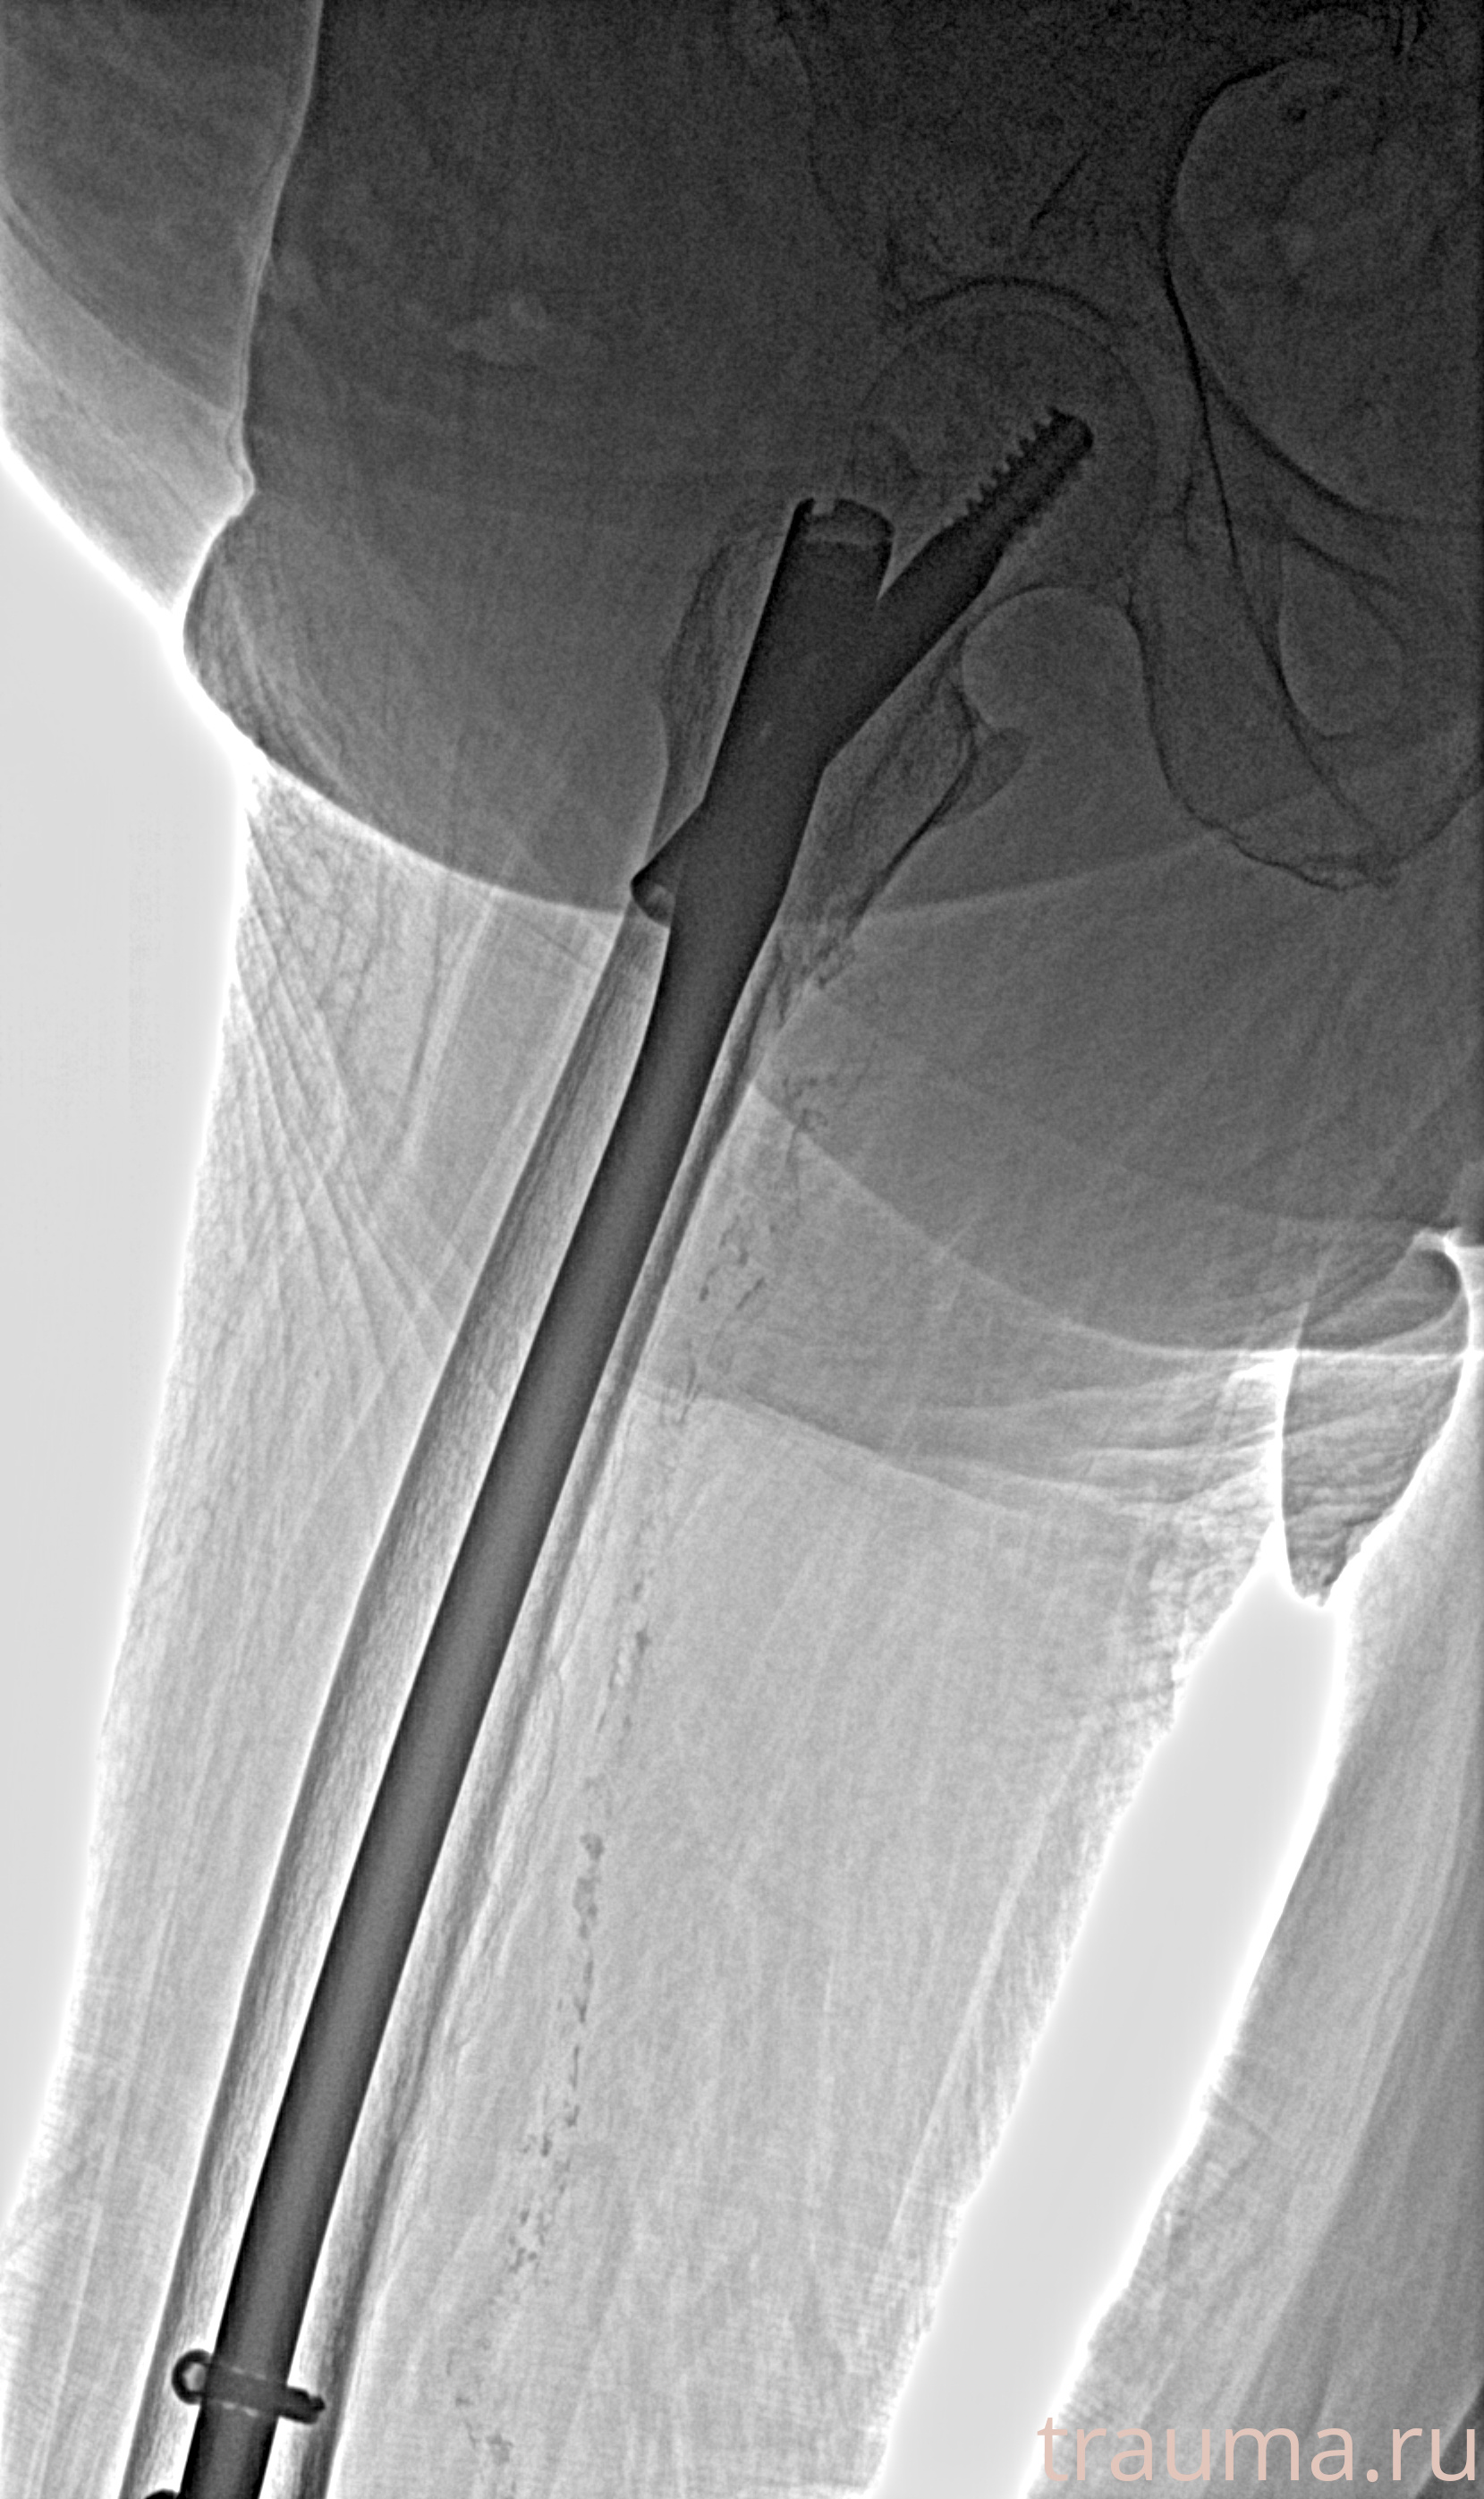

Рентгенограммы

Рентген на дому: по вашему адресу приезжает врач-рентгенолог, травматолог-ортопед с мобильным рентгеновским аппаратом, проводит диагностику травмы или заболевания, делает необходимые рентгенограммы, дает рекомендации по дальнейшему лечению. Получить качественные снимки в домашних условиях возможно благодаря уникальной методике, разработанной МосРентген Центром для института  Склифосовского